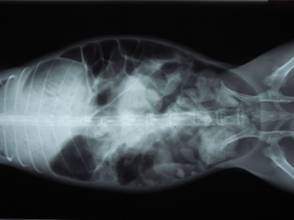

ウサギが「腸管うっ滞」をおこすと元気がなくなったり、食欲が低下したり、下痢をしたりします。

これは腸内の細菌叢に異変が起こった結果、腸内に毒素が発生して、腸毒素血症にいたる病気です。

上手に治療すれば、治りますが、この毒素が全身に回って組織壊死を起こすと死に至ります。

治療として、強制給餌や消化機能改善薬やマッサージや点滴や腸管内のガスの吸引等を行います。

原因で一番多いのは毛玉による「胃毛球症」です。